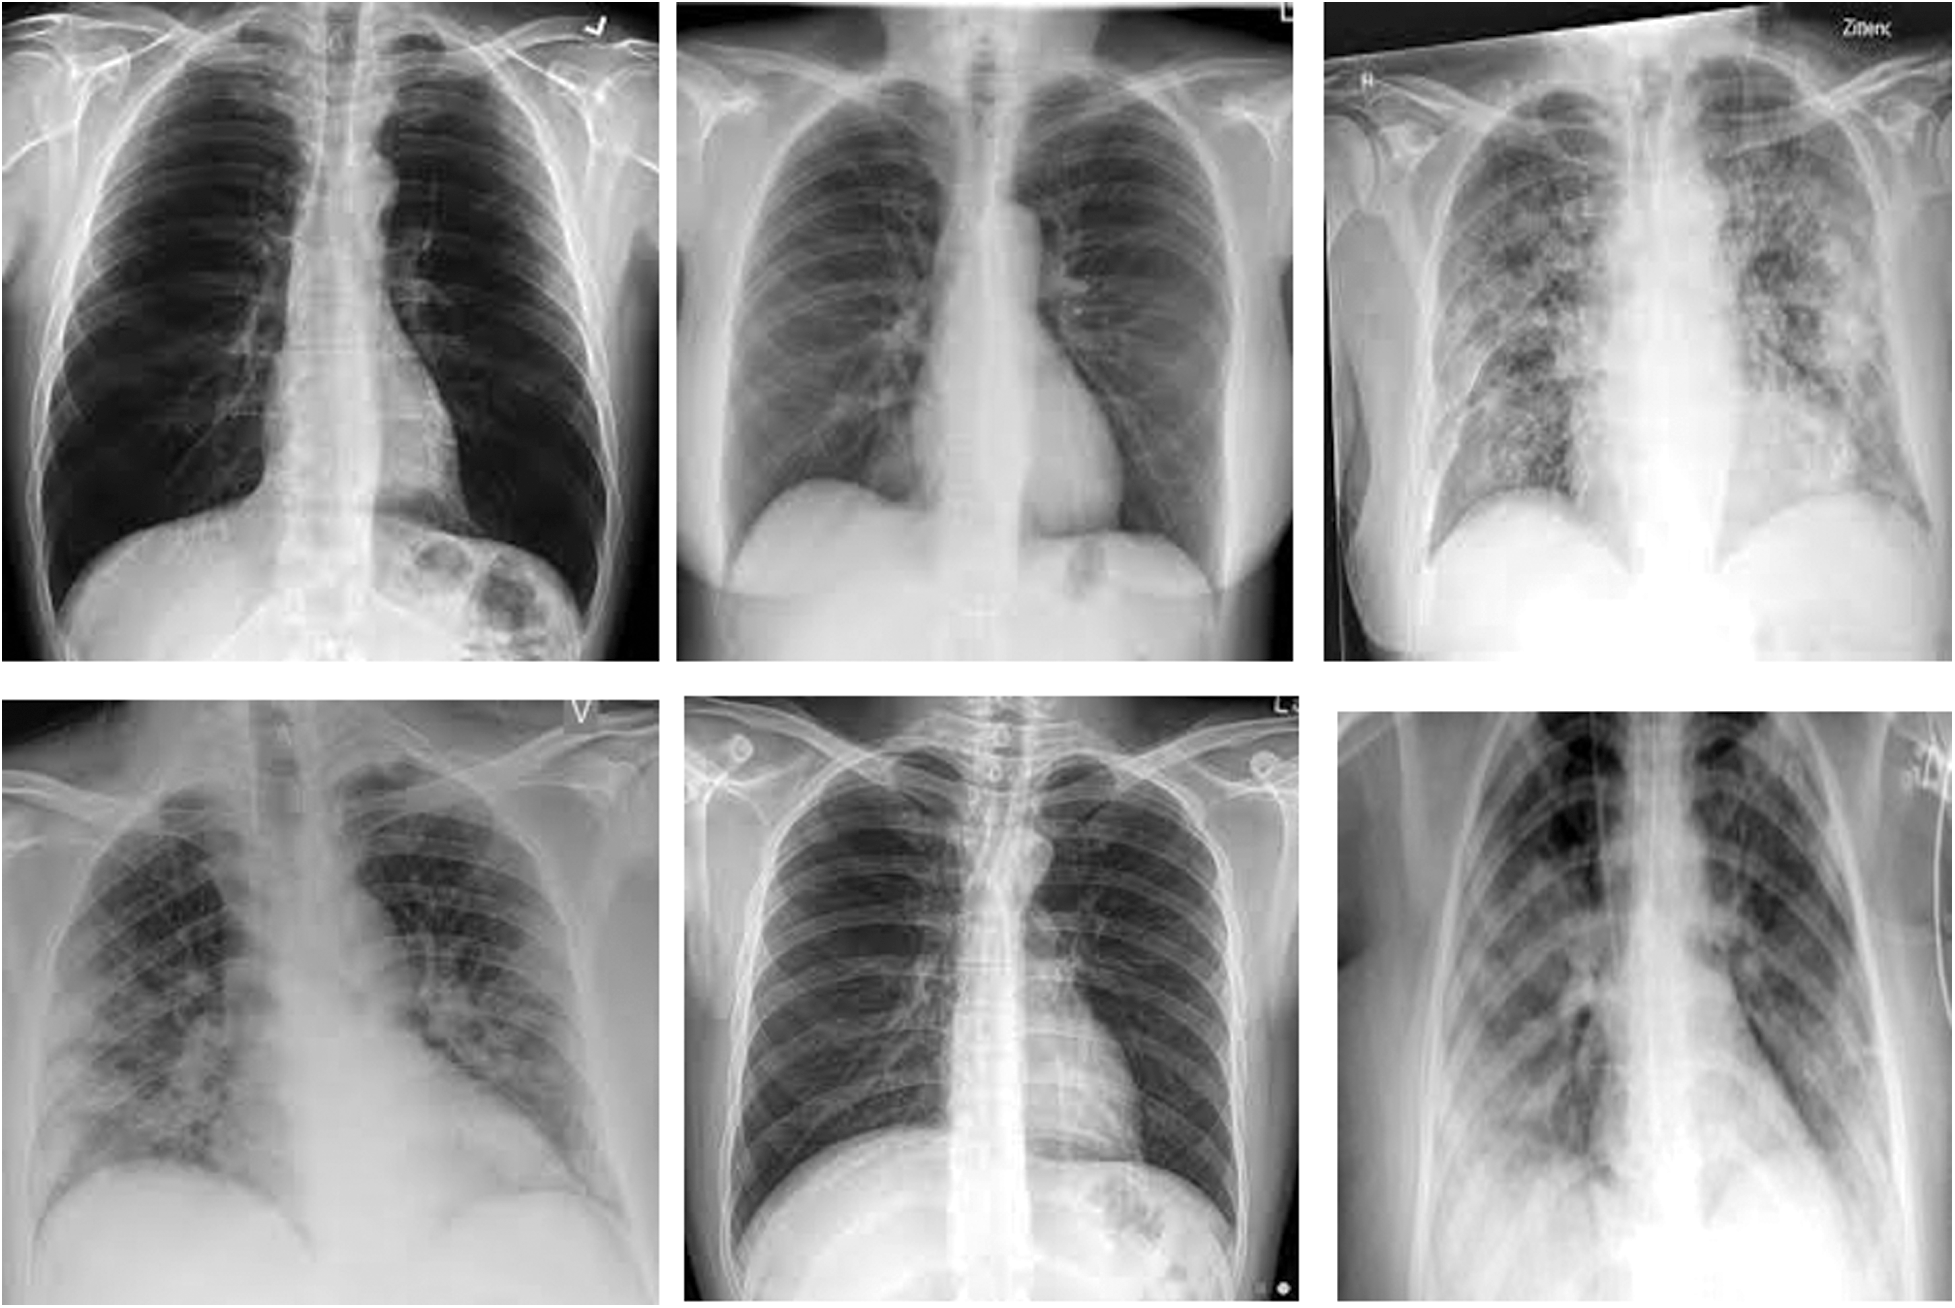

Tab. 1 tabulates the data of CXR images for both the datasets. During preparation, the COVID-19 positive X-ray are considered while the patients’ ages was in the range of 12–93. Likewise, the researcher also considered the COVID-19 and non-COVID-19 chest X-ray images. In any case, a total of 402 images was considered (same as COVID-19 chest X-ray images) whereas the researcher also considered ordinary chest X-ray images for preparation and testing purposes. In dataset 2, the study considered 954 images for training as well as testing purposes. Fig. 3 portrays the CXR images collected from GitHub storehouse.

Figure 3: CXR images from github repository